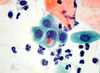

3

Q

A

3 Trichomonas vaginalis